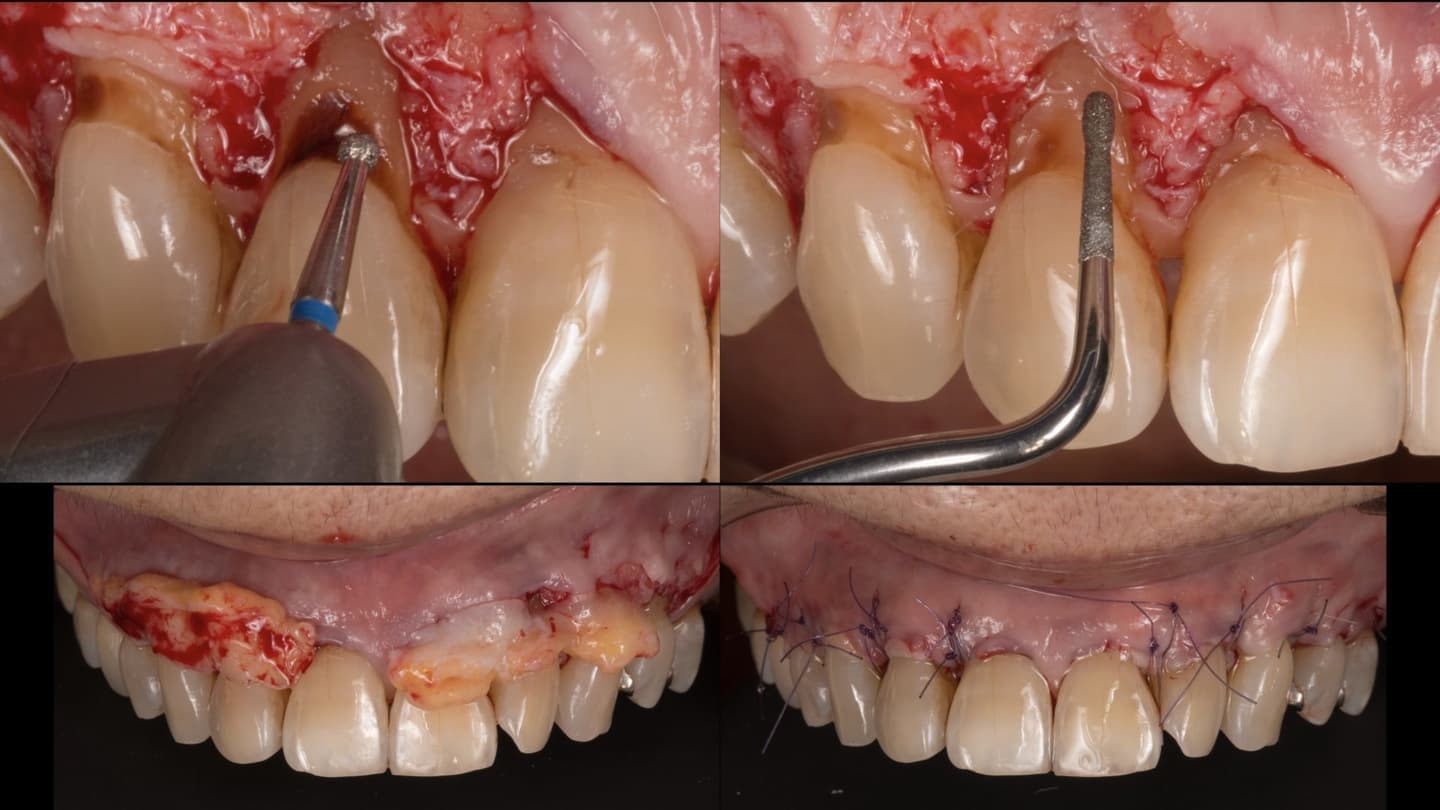

専門医ではないと対応できない症例もあります

指導医として若い専門医への指導も行っています。最新の文献、情報には常に目を通しています

歯周組織再生を基礎研究から生涯のテーマとして取り組んできました